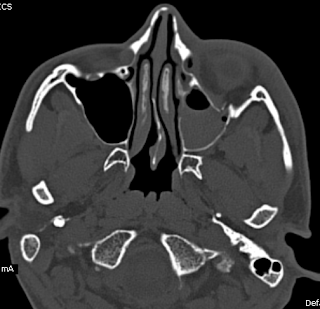

Blow Out Fracture-MDCT

A young adult with history of injury to the left face with diplopia and restricted gaze, shows on the multidetector CT (128 slices), an orbital floor fracture with inferior rectus intrapment with a chip of the communited component lying as a satellite piece.

Smith and Regan described blowout fracture in 1957, as orbital floor fracture (maxillary / zygomatic / palatine bones constitute the floor measuring 35 to 40 mm and shortest of all the walls, not reaching upto the orbital apex). Second most common mid facial fracture after nasal bones.

Mechanism usually involves impact injury, large enough not to perforate the globe and small enough not to fracture orbital rim.

Leads to increase in intraorbital hydrolic pressure.

Most occur in posteromedial region which is the thinnest and medial to the infraorbital groove.

Orbital emphysema, intraorbital bleed, inferior rectus entrapment, globe injuries including Hyphaema, retinal injury are possible accompaniments.

CT delineates the fracture including any associated fractures like zygomatic / lefort type II / III, and fracture orbital rims.